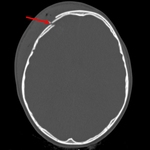

Comminuted nondepressed fracture

From the teaching collection of Demetrios Demetriades; used with permission